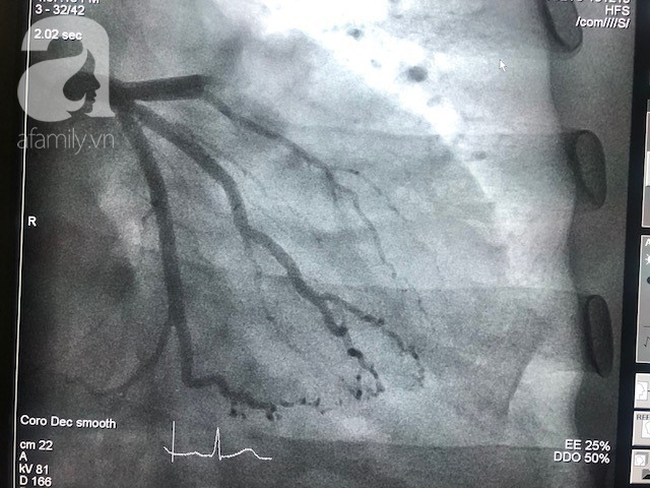

Giáo sư Ernesto Maddalony (Italia) cho biết, ĐTĐ là căn bệnh không lây, diễn tiến âm thầm nên người dân thường chủ quan, khi phát hiện bệnh thì tình trạng đã nặng. Nhiều trường hợp gây những biến chứng đến thận, bệnh tim mạch, nhồi máu cơ tim…